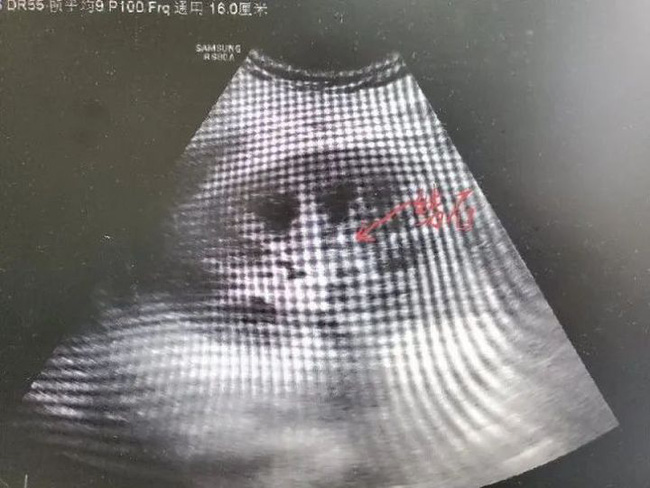

Lý Khải còn bị sỏi thận

Xét thấy bệnh tình nghiêm trọng của Lý Khải, bác sĩ Triệu Ninh đã kịp thời tiến hành chạy thận nhân tạo cho anh để giúp thận loại bỏ chất độc ra khỏi cơ thể. Đồng thời, làm sinh thiết thận, ông rất ngạc nhiên khi phát hiện có nhiều nốt vôi hóa ở ống thận, và các tế bào biểu mô ống thận xung quanh chỗ bị vôi hóa, siêu âm thận cũng cho thấy sự hiện diện của nhiều viên sỏi thận.